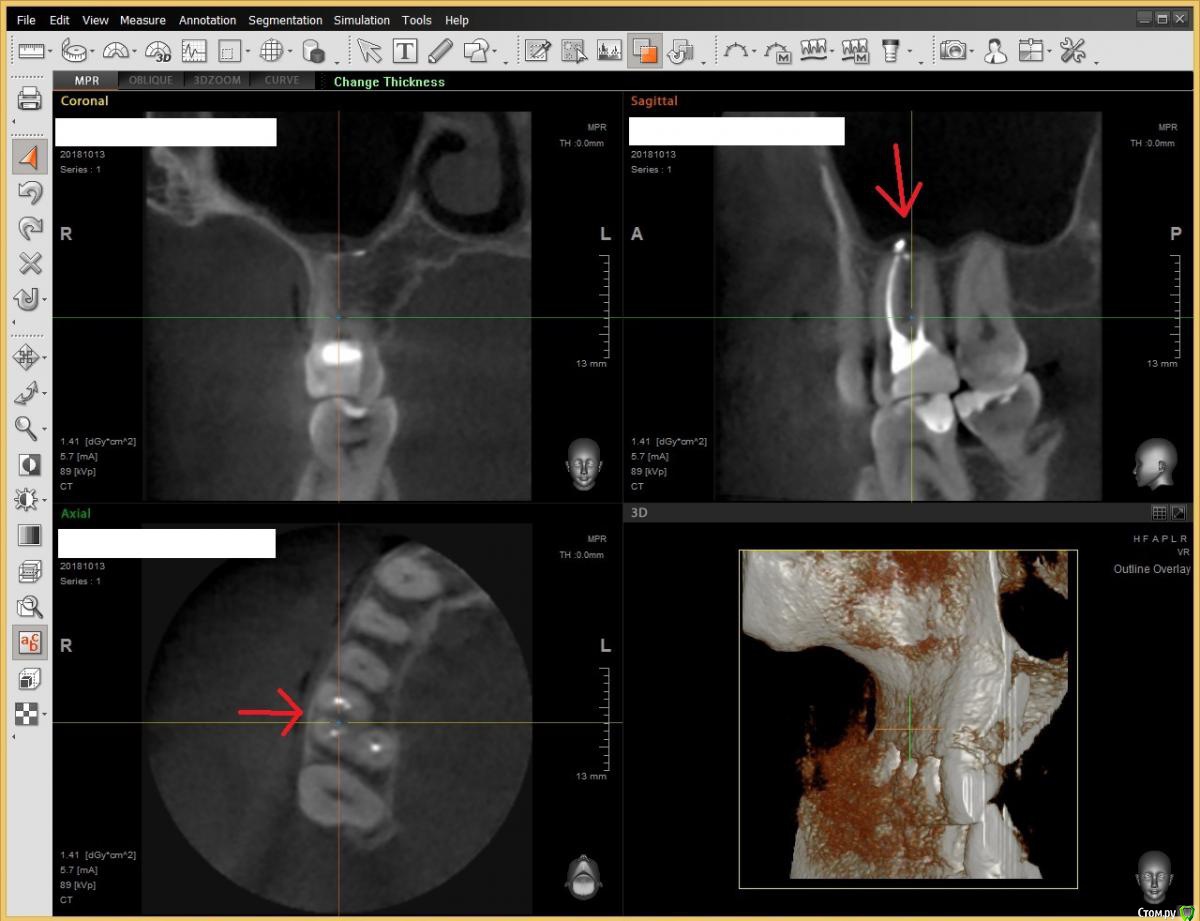

usilitel Опубликовано 19 ноября, 2018 Автор Поделиться Опубликовано 19 ноября, 2018 (изменено) Проб на токисчность не существует.ОЧЕНЬ ПЛОХО. Было бы полезно делать такие пробы (для выявления криворуких стоматологов). Вы, стоматологи, не обижайтесь, но я подозреваю что именно поэтому такие пробы и не делают (иначе выяснится что половина стоматологов не лечат, а калечат, лично насмотрелся на таких).Кстати заодно вопрос - почему такую ответственную операцию как засвечивание пломбы доверяют ассистентам? Может вы, врачи, на себя ответственность брать не хотите? А люди потом мучаются из-за несоблюдения технологии. И не докажешь ничего (пломба же стоит, не вываливается). Руки бы оторвал.(извините, наболело) после перелечивания прошли изменения в пазухе.Воспаление в пазухе прошло не после перелечивания, а само, через 2 недели после депульпации. сколько времени после лечения прошло?Хронология такая:- 9 месяцев назад сделали депульпацию.- Через 3 дня после депульпации сделал снимок - обнаружилось воспаление слизистой гайморой пазухи.- Еще через 2 недели сделал 2-ой снимок - воспаление слизистой прошло.- 7 месяцев назад перелечивали (обнаружили незапломбированный канал mb2). При перелечивании кусок пломбировочного материала и немного гуттаперчи вышло в гайморову пазуху (но остались под слизистой).- 3 месяца назад перелечивали 2-ой раз (обнаружили что нёбный канал был не до конца запломбирован). Всё это время (то есть 9 месяцев уже) 6-ой зуб беспокоит (симптомы перечислил в 1-ом посте). Плюс 1 месяц назад начал болеть соседний 7-ой зуб, и в нем под пломбой очень быстро начал прогрессировать кариес. Плюс под ними 2 зуба (нижние 6-ой и 7-ой) стали беспокоить (тоже начал кариес под пломбами быстро прогрессировать и в 6-ом зуд появился). Изменено 19 ноября, 2018 пользователем usilitel 2 Ссылка на комментарий

usilitel Опубликовано 21 ноября, 2018 Автор Поделиться Опубликовано 21 ноября, 2018 Сегодня немного воспалилась верхняя десна в области корней 4,5 и 7-го зубов (у 6-го зуба не воспалилась). Испугался, пошёл уже вырывать зуб, но хирург отговорила, сказала что лучше сначала сходить к ЛОР-у, чтобы он эндоскопом вынул пломбировочный материал из гайморовой пазухи. Во-первых - причина симптомов может быть в инородном теле в гайморовой пазухе, во-вторых - при удалении зуба всё равно этот кусок в гайморовой скорее всего останется, и его всё равно придется удалять.Пойду к ЛОР-у, посмотрим что скажет. Ссылка на комментарий